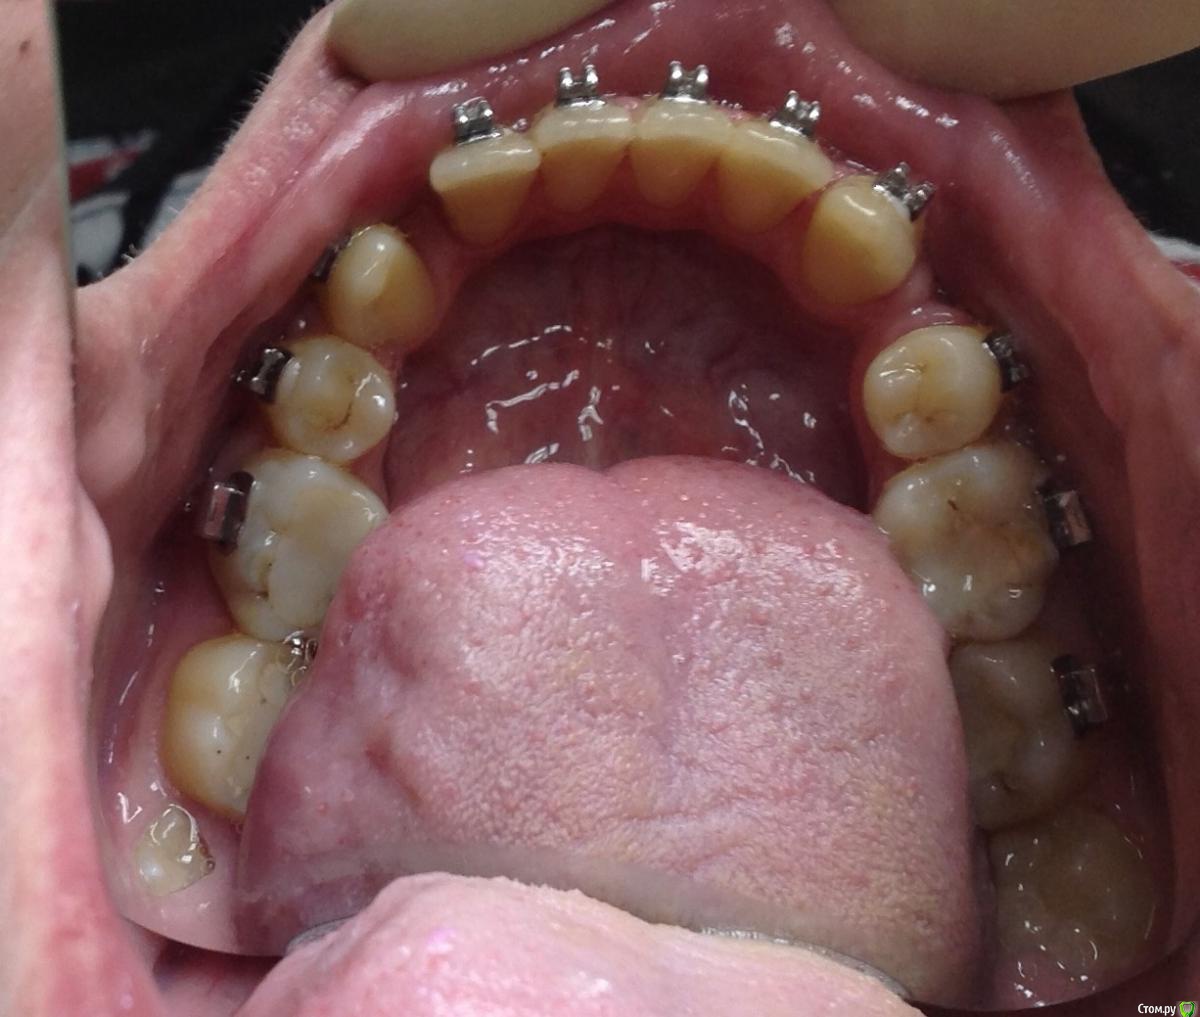

KoroNa Опубликовано 13 января, 2015 Поделиться Опубликовано 13 января, 2015 Здравствуйте. Опыт у меня совсем небольшой, можно даже сказать никакой на данном этапе. Пациент достался "по наследству" от подруги. Приехал учиться в наш город, она и пристроила мне. Я делала свое дело, меняла лигатурки, зная, что пациент периодически ездит в свой город и будет контроль лечения со стороны моей коллеги. А та, не долго думая, в декрет укатила с двойней. Когда увидела пациента, то как РАДА НЕ БЫЛА - ничего не сказать.3класс. вертикальный тип роста. Явные признаки к комплексному орто\хир лечению. Но она взялась, пожалела\попросили.....удалила премоляры на н\ч и начала дистализацию. Никаких ТРГ и моднлей в помине нет, да и я еще когда брала его даже фотографии не делала.Не хочу на форуме ругаться, но пациент "какашка" .......гигиенты нет как в полости рта, так и на лице...пропуски приемов....и т.д.НО! Подруге пообещала....Я сразу написала, что опыта ноль, только благодаря нашим лекторам стала сейчас обращать внимание на симметрию, на сустав и т.д. И вот, заходит пациент, на очередную смену лигатур, такой красивый в кабинет и что я вижу.....нижняя челюсть смещена влево, явная асимметрия. Куда мои глаза и мозги смотрели. Очень прошу помочь мне советами, что сейчас нужно сделать, с чего начать Ссылка на комментарий

KoroNa Опубликовано 20 января, 2015 Автор Поделиться Опубликовано 20 января, 2015 Думаю паниковать пока рано. Такое иногда бывает при значительном перемещении зуба/зубов, когда возникают контакты бугор-в-бугор, а н.ч отвечает компенсаторным смещением в ту или иную стогону. Если ЦЛ н.ч при максимальном оркрывании рта мигрирует, то всеОК. В любом случае проведите полную диагностику, а ОПТГ сейчас сделайте в положении ЦО (при полном/максимальном смыкании зубов). Это даст возможность оценить симметрию СГ.PS с какой целью стоит лингвальная кнопка на в.ч, носит ли пациент эластики и если да то как?Здравствуйте.Центральная линия при максимальном открывании рта практически "централизуется", но там есть еще и смещение ЦЛ из-за миграции резцов влево."ОПТГ сейчас сделайте в положении ЦО (при полном/максимальном смыкании зубов" - т.е. объяснить пациенту чтобы сомкнул рот на все зубы как смыкает обычно? не нужно смещать челюсть и делать прикусной шаблон?Кнопка справа на 6ом моляре применялась для устранения перекрестной окклюзии. пациент оторвал замок и около месяца не появлялся на прием. вот зуб и уехал. Ссылка на комментарий

KoroNa Опубликовано 23 января, 2015 Автор Поделиться Опубликовано 23 января, 2015 Кнопка справа на 6ом моляре применялась для устранения перекрестной окклюзии. пациент оторвал замок и около месяца не появлялся на прием. вот зуб и уехал. Что значит "уехал" , а конкретнее куда?Спасибо за ваши комментарии. Зуб 1.6 "ушел" в небную сторону -палатиноокклюзия, если не ошибаюсь. Ссылка на комментарий